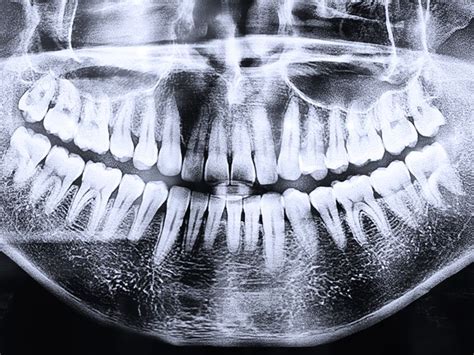

Todo comienza con una consulta de valoración. En esta cita evaluamos el estado de tu diente y encía, generalmente con una radiografía panorámica o TAC 3D. Decidiremos si la muela es irreversible y debe extraerse, y planificaremos la colocación del implante.

Si la pieza dental está muy dañada por caries, fractura o infección, procedemos a la extracción (exodoncia). Este es un acto quirúrgico menor que realizamos con anestesia local, asegurándonos de que no sientas dolor. Tras sacar la muela, valoramos el estado del hueso alveolar.